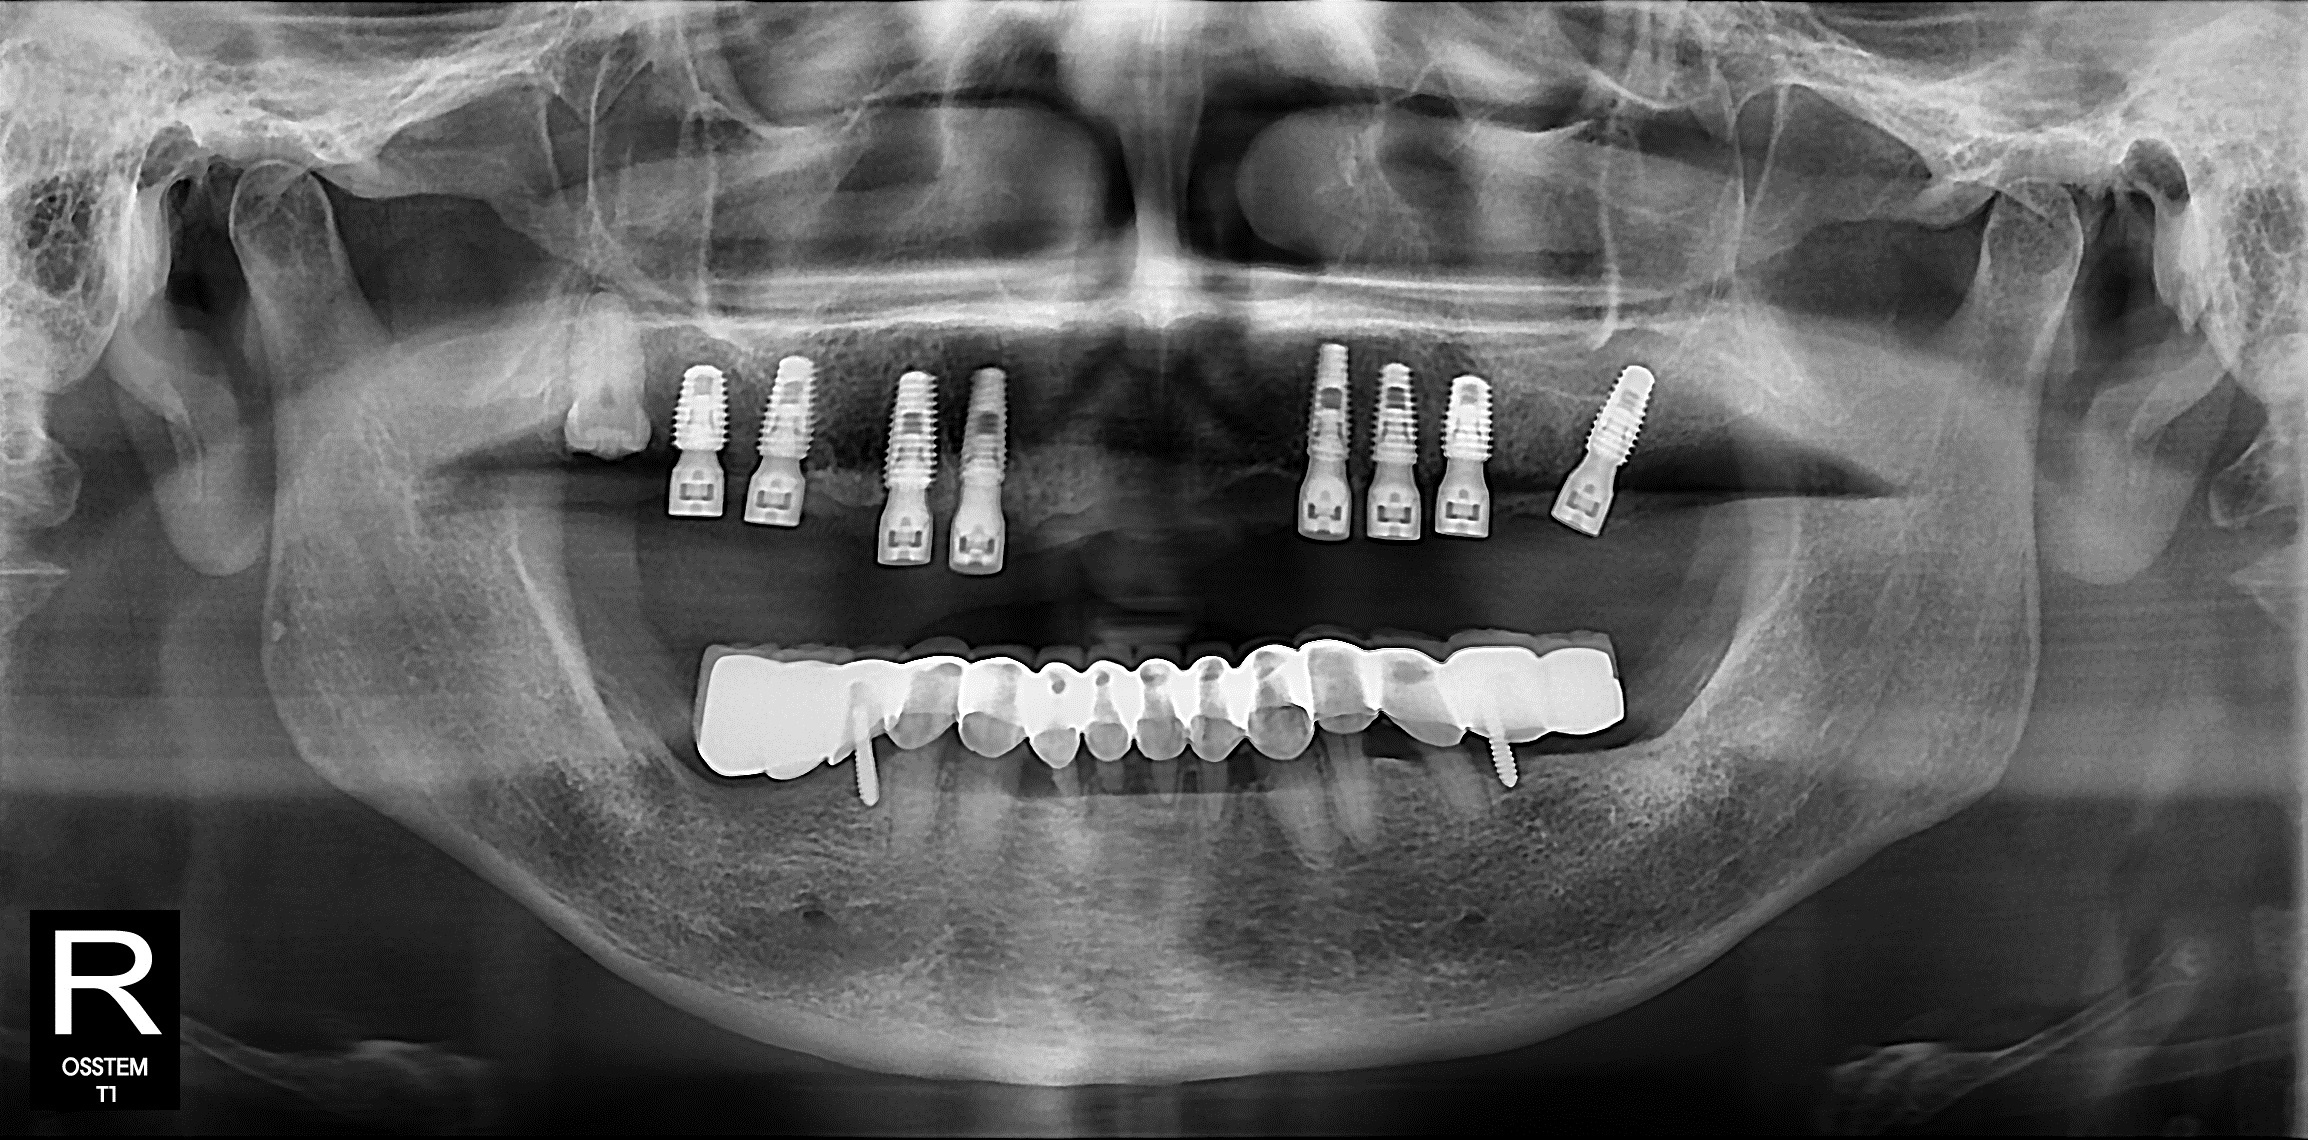

엑스레이를 보니

금세 이유를 알 수 있었습니다.

신경치료가 되지 않은 치아 위에

보철이 덮여 있었고,

기둥 역할을 하던 치아들은

염증으로 흔들리고 있었습니다.

브릿지 아래쪽은

염증과 뼈 손실이 진행된 모습이

확인되었습니다.

그렇기에 하루임플에서는

상악 풀브릿지 제거 후

8개 임플란트를 식립하기로 했습니다.

남아 있는 잇몸뼈를 기준으로

양쪽 소구치와 대구치 부위에

총 8개의 임플란트를

식립했습니다.

양쪽으로 고르게 분산시켜

씹는 힘을 안정적으로 분배 하고,

잇몸에 무리 가지 않게

설계한 구조입니다.